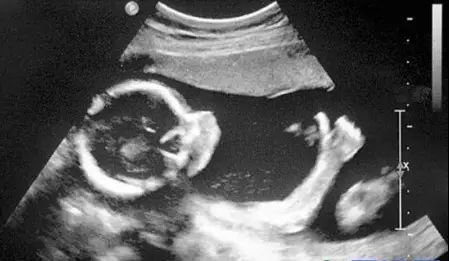

B超对于人体管腔的液体流动和腹腔脏器检查的敏感性较高,我们常常遇到的胆囊结石,肾结石,血管狭窄,心脏功能等等检查,都是B超的用武之地。B超有着独特的优势,便携,可以在床边,甚至在手术中使用。此外,B超市利用超声波成像,也没有所谓的辐射。所以孕妇多采用B超检查。